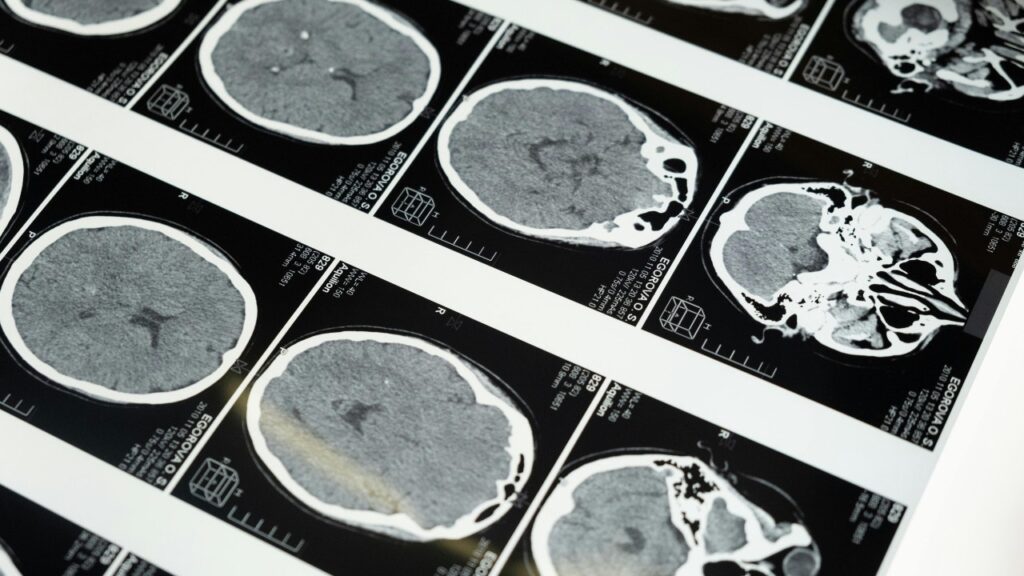

Brain imaging highlights the regions researchers study as companies explore noninvasive ultrasound brain-computer interface technology. (Kurt “CyberGuy” Knutsson)